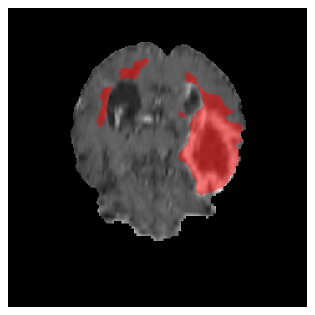

Appendix A Qualitative results

Figures 4 and 5 present the segmentation results for a patient from the BRATS dataset, visualized on a randomly selected slice. Figure 4 illustrates how tumor segmentation evolves over multiple episodes in S1 across different approaches including cumulative, naive, our approach, and the best buffer-free strategy (SI, =2). The cumulative approach, which trains on all encountered datasets together, maintains segmentation consistency across episodes but introduces significant amounts of false positives, particularly in the upper left area of the brain images. These misclassifications highlight its inability to generalize well across datasets despite access to all previous data. The naive approach, which learns sequentially without any continual learning strategy, suffers from severe catastrophic forgetting. While it initially segments well, performance deteriorates over episodes, leading to a near-complete loss of segmentation capability by the final episode. The SI (=2) approach, a regularization-based buffer-free CL strategy, performs reasonably well in early episodes but shows a significant performance decline over time. By the last episode, much of the tumor was no longer segmented, indicating difficulty in retaining prior knowledge. In contrast, our proposed approach initially produces more false positives but progressively refines its segmentation. By the final episode, it accurately retains the tumor region while minimizing misclassifications, demonstrating strong knowledge retention and adaptability across episodes. This suggests that our approach effectively mitigates catastrophic forgetting while maintaining segmentation performance over sequential learning.